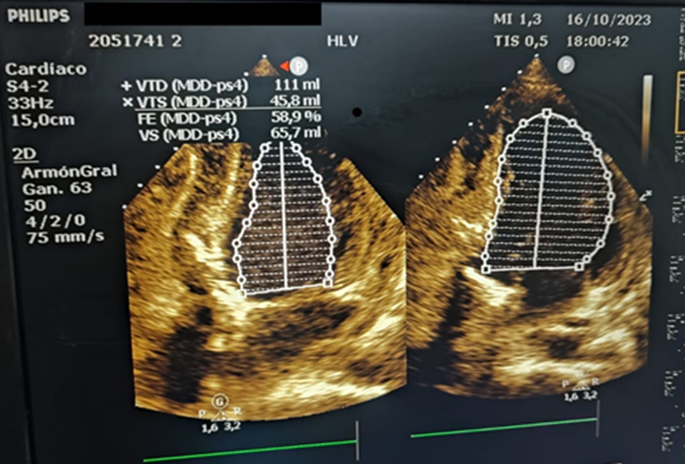

Aproximadamente 3 Semanas posterior al alta presenta cuadro de insuficiencia respiratoria asociado a insuficiencia cardiaca descompensada por lo que acude a nuestro Hospital de Especialidades Abel Gilbert Pontón siendo internada en Unidad Coronaria, a su ingreso se evidencia dolor precordial y torácico bilateral que irradia a región dorsal acompañado de disnea clase funcional NYHA IV/IV, tos persistente y edema leve de miembros inferiores, los laboratorios realizados evidencian anemia leve con hb 10.8 g/dL, péptido natriurético elevado de 12895 pg/ml, enzimas cardiacas negativas, hematuria y proteinuria en uroanálisis; en la radiografía de tórax se muestra cardiomegalia y derrame pleural bilateral; En electrocardiograma taquicardia sinusal, dextrorrotación, complejo QS en cara inferior, sin alteraciones de la onda T y segmento ST. En eco de pleura muestra derrame pleural derecho de moderada a gran cuantía y derrame pleural izquierdo moderado, sospechando de colagenopatía vs enfermedad autoinmune a descartar. Se realiza ecocardiograma transtorácico se evidencia formación aneurismática del VI de 9.5cm x 9.7cm tapizado por trombos con pérdida de la continuidad a nivel perimembranoso septal, además de una miocardiopatía dilatada con FEVI (fracción de eyección del ventrículo izquierdo) 28%. El estudio de líquido pericárdico da como resultado exudado con relación líquido/sérica de LDH 1,8 y proteína 0,7. En ecocardiograma transesofágico (Ilustración 1,2,3) se confirma pseudoaneurisma de gran tamaño del VI en región basal posterior con flujo bidireccional de 10 cm x 7,22cm tapizado de formación trombótica con pérdida de la continuidad de la región basal y posterior del VI con hipocinesia global e hipertensión pulmonar leve con insuficiencia mitral y tricuspidea leve por lo que se decide resolución quirúrgica.

El tratamiento consistió en reparación quirúrgica del pseudoaneurisma usando parche de Dacron para tapizar el sitio de ruptura miocárdica cubriendo parte del septum y segmento posterior, se realiza ecocardiograma transquirúrgico.

Ilustración 6 Evidencia mejoría inmediata de la FEVI 58%.

Fuente: Hospital de Especialidades Guayaquil “Doctor Abel Gilbert Pontón”.